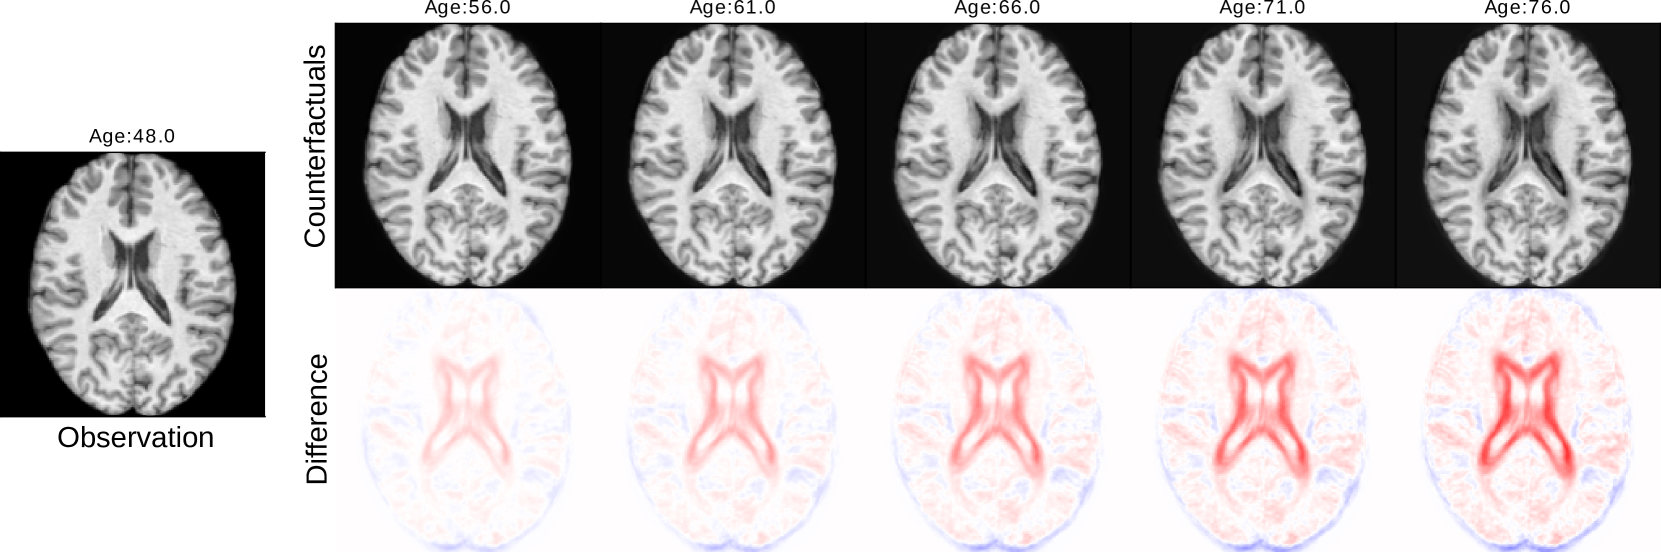

Counterfactual inference was performed on data points within the test set. Using this setup, we aimed to estimate how an image would appear if the person had different biological characteristics, including age, sex, and BMI. Counterfactuals were generated independently for each model and then reconstructed, following a process similar to the generative sampling. Figure 5 visually demonstrates that age has an expected impact on the ventricular and sulci regions. Increasing the age tends to enlarge the ventricular area while decreasing the age variable reduces the ventricular volume. Furthermore, changes in the sulci regions are also observed when changing the age variable. When considering sex-related counterfactuals, variations in brain size and subtle changes [28] in the ventricular regions can be observed in the figure. Furthermore, when generating counterfactual images to illustrate sex differences, the BMI values appropriately change, with males exhibiting higher BMI values. This is attributed to the causal influence of sex on BMI. Finally, BMI changes result in alterations of the lateral and ventricular parts of the brain, which may be related to accelerated brain aging [29]. In addition, Fig 6 displays results from counterfactual queries simulating brain aging.

Refer to caption

Figure 6: Results from counterfactual queries simulating brain aging. Each counterfactual image corresponds to a unique query “do(Age=x)𝑑𝑜𝐴𝑔𝑒𝑥do(Age=x)italic_d italic_o ( italic_A italic_g italic_e = italic_x )”.